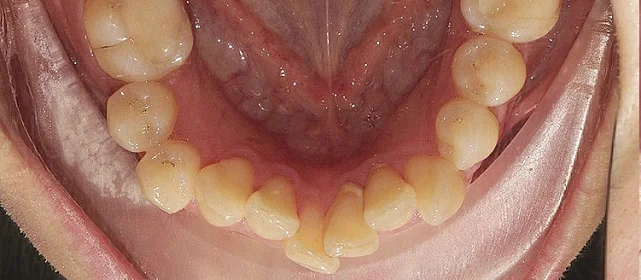

Неправильное положение зубов, неправильное смыкание.

Нарушение соотношения челюстей и неправильное положение зубов — зубные ряды смыкались некорректно, зубы стояли со смещением.

Проблема: Пациентку беспокоило неправильное смыкание зубов и их положение — ряды не сходились как нужно, зубы стояли со смещением. Это влияло и на внешний вид, и на то, как распределялась нагрузка при жевании.